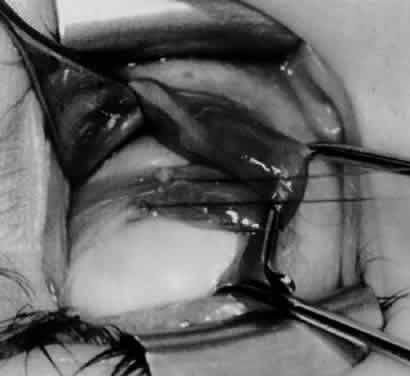

Fig. 17. Knots are tied to show the placement. The inferior oblique muscle is held on a Stevens muscle hook.

Fig. 18. The final position, with the inferior oblique muscle recessed 10 mm. The inferior rectus muscle is retracted with a Green muscle hook. As described in the text, the 14-mm recession would place the inferior oblique muscle over the inferior temporal vortex vein, and the 6-mm recession would place the inferior oblique muscle anterior and nasal to this position.

Fig. 19. A 14-mm inferior oblique muscle recession is placed over the inferior temporal vortex vein.